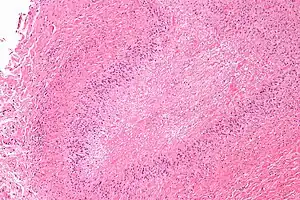

| Micrograph of a rheumatoid nodule, showing the characteristic palisading granuloma with a core consisting of necrotic collagen and fibrin. H&E stain. | |

Histological examination of nodules shows that they consist of a shell of fibrous tissue surrounding a center of fibrinoid necrosis.[13] Pea-sized nodules have one centre. Larger nodules tend to be multilocular, with many separate shells or with connections between the necrotic centers. Individual necrotic centers may contain a cleft or several centers of necrosis may all open on to a large bursal pocket containing synovial fluid.

The boundary between the necrotic center and the outer fibrous shell is made up of the characteristic feature of the nodule, which is known as a cellular palisade. The palisade is a densely packed layer of macrophages and fibroblasts which tend to be arranged radially, like the seeds of a kiwifruit or fig.[13] Further out into the fibrous shell there is a zone that contains T cells and plasma cells in association with blood vessels.[14] The histology of pulmonary nodules are similar to that of subcutaneous nodules, with central necrosis surrounded by palisading macrophages and inflammatory infiltrate.[5]